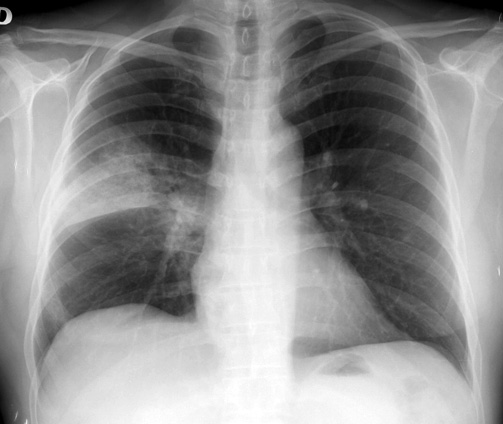

La vacuna redujo en un 33% las neumonías por serotipos incluidos en la vacuna, y en un 27% el total de neumonías por neumococo en esta población. Lancet Infectious Diseases, 23 de enero de 2017